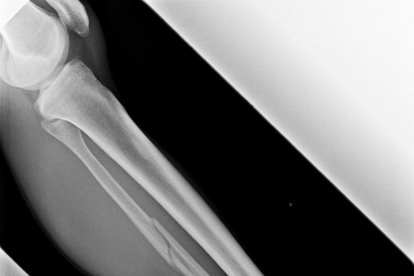

“Després de la caiguda i sabent com és, es va aixecar per seguir, però no era possible. Espero que no sigui gaire greu”, va dir l’austríac, que va tornar sol a la zona de meta, amb els esquís de Jornet. Unes hores més tard, el mateix Jornet va publicar a Twitter una fotografia d’una radiografia en la qual s’aprecia una evident fractura de peroné.